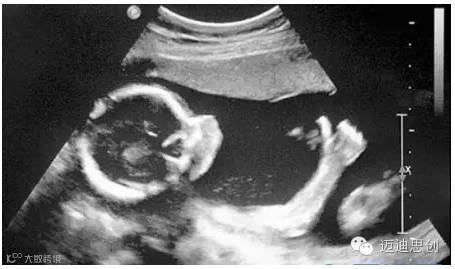

4、腹部盆腔——除肠道外,一般超声都能查

腹腔器官受呼吸影响较大,进而影响到CT、核磁成像,而超声不会因此受影响。同时,超声对肝脏、脾脏、胰腺、肾脏、盆腔脏器等诊断准确率较高。

但是,超声受气体干扰很大,对于肠道等含气较多的器官,超声诊断准确率会降低。